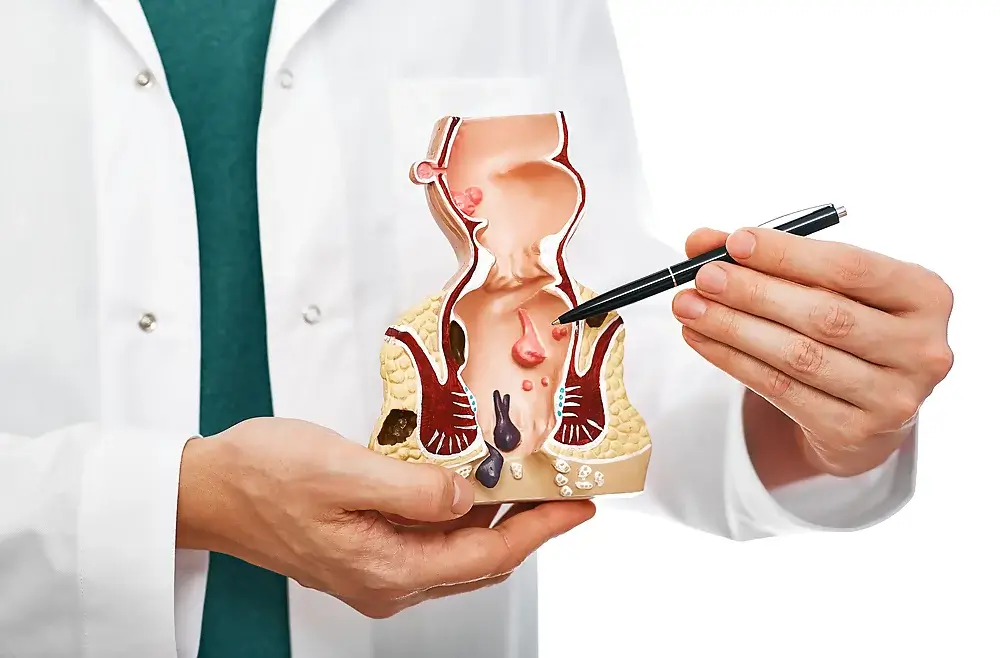

- Hemorrhoids • Georgetown • Naturopath • Natural Health Clinic of Halton (March 19, 2017)

Healthy Gut

The digestive system is responsible for breaking down and for the absorption of micro/macronutrients necessary to sustain, regenerate and repair the body. It is also the powerhouse of most of the body’s immune system, thus a healthy gut leads to a strong immune system.

The digestive system is also one of our main detoxification organs. It absorbs the nutrients required for the body and eliminates both intrinsic toxins – toxins or byproducts pro...